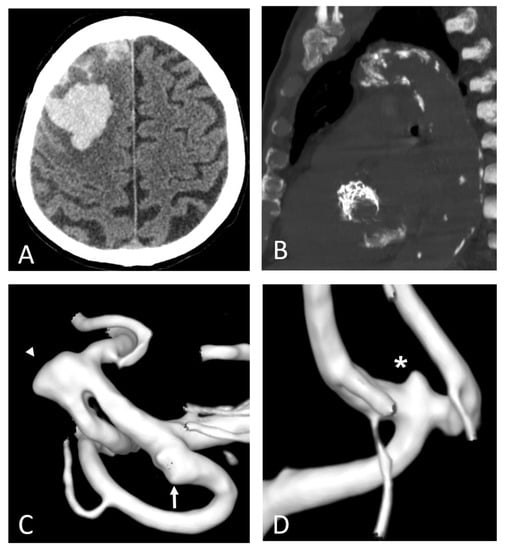

Figure 7.

Polyvascular disease: right frontal lobar haemorrhage due to cerebral amyloid angiopathy (A) in an 82-year-old man with a prosthetic aortic valve and extensive calcifications of the aortic arch and along the descending thoracic aorta (B). Three-dimensional digital subtraction angiography reconstructions of the same patient (C,D) show diffuse arterial dysplasia with ecstatic origin of an inferior temporal branch (arrow), a dysmorphic aneurysm of the Sylvian bifurcation of the middle cerebral artery (arrowhead), and an infra-millimetric aneurysm of the anterior communicating artery (*).